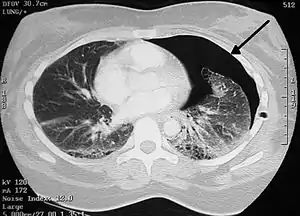

![]() Правосторонний спонтанный пневмоторакс (слева на изображении). Стрелкой указан край спавшегося лёгкого. | |

- Рентгенографическим признаком пневмоторакса является визуализация тонкой линии висцеральной плевры (менее 1 мм), отделённой от грудной клетки.

- Для диагностики небольших по размеру пневмотораксов КТ является более надёжным методом по сравнению с рентгенографией.

- Для дифференциального диагноза больших эмфизематозных булл и пневмоторакса наиболее чувствительным методом является КТ.

- КТ показана для выяснения причины вторичного спонтанного пневмоторакса (буллёзная эмфизема, кисты, интерстициальные болезни лёгких и др.).